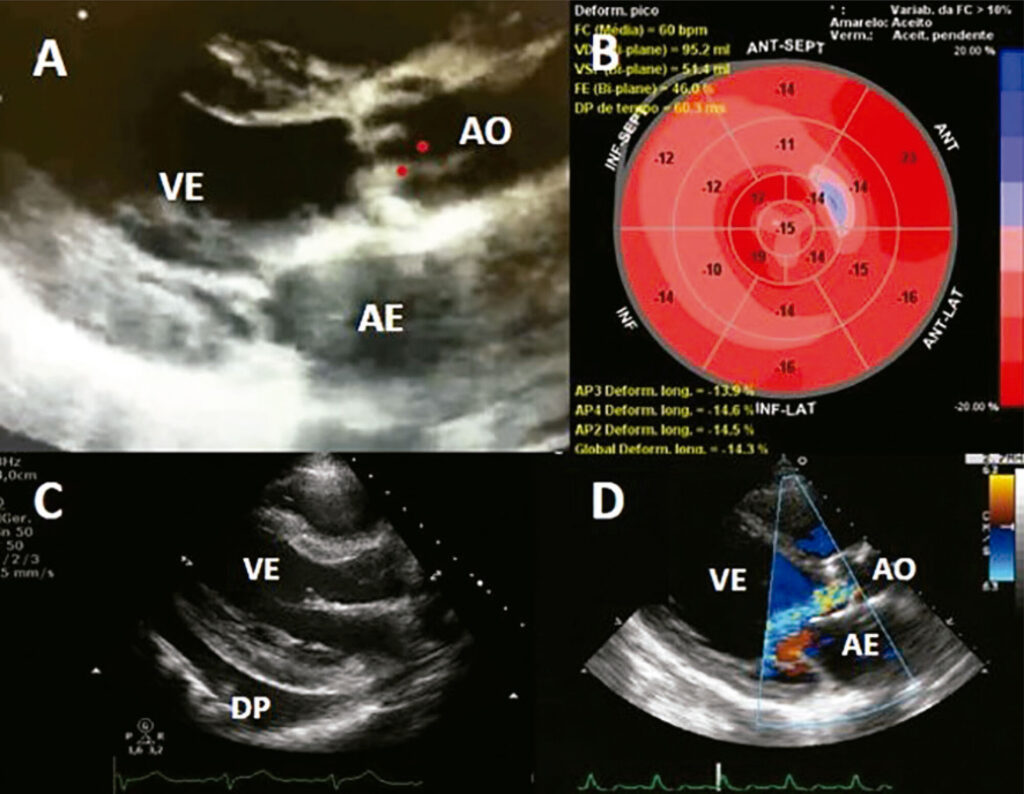

Cardiopatia Induzida por Radioterapia: O que Podemos Avaliar?

A radioterapia (RT) faz parte do tratamento oncológico desde 1899, sendo utilizada atualmente em mais de 50% dos pacientes. Tumores de mama, pulmão, esôfago e linfomas são frequentemente submetidos ao tratamento por RT, apresentando melhora na sobrevida total e livre de doença. Por outro lado, ao incluirmos estruturas mediastinais como coração e os vasos próximos, observamos, em 10 a 30% dos pacientes, a ocorrência de eventos cardiovasculares adversos após 5 a 10 anos, designados de cardiopatia induzida por radioterapia (CIRT).,

O espectro da CIRT inclui doenças pericárdicas, doença arterial coronariana, doença orovalvar, cardiomiopatia, anormalidades de condução e disautonomia, levando a aumento da morbidade e mortalidade cardiovasculares nos sobreviventes.